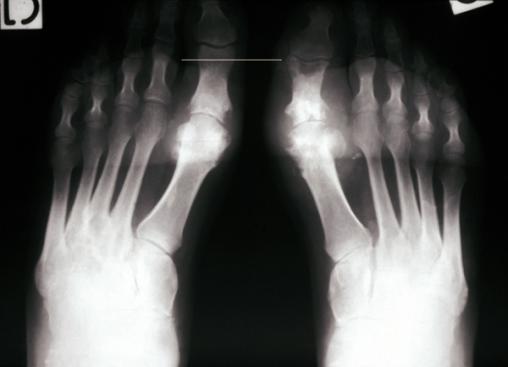

© Gérard Chalès, Pascal Guggenbuhl (La Revue du Praticien) Radiographie avant-pied pied (face). Goutte : encoches épiphysaires, aspect en hallebarde, interligne conservé. Voir : Chalès G, Guggenbuhl P. Arthropathie microcristalline. Rev Prat 2013;63(5):709-20.